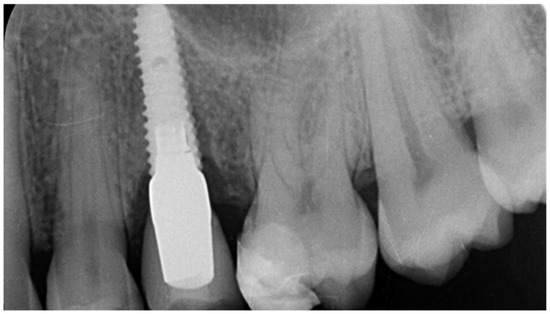

- Velásquez-Plata, D.; Lutonsky, J.; Oshida, Y.; Jones, R. A close-up look at an implant fracture: A case report. Int. J. Periodontics Restor. Dent. 2002, 22, 483–491. [Google Scholar]